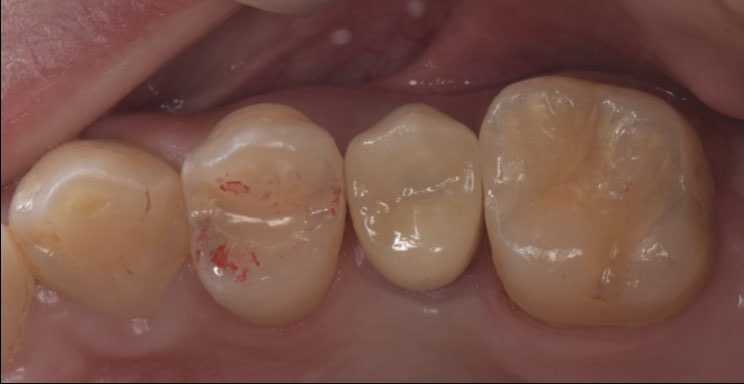

欠損した歯をインプラントで治療した症例

Before

After

| 治療内容 | インプラント治療 |

| 治療期間・治療回数 | 2ヶ月半 |

| 治療費用 | 528,000円(税込) |

| リスク・副作用 | 外科処置を伴います。 |

| 備考 | 治療方法や費用、治療期間などは、ケースによって異なります。患者さまに合わせた治療計画をカウンセリング時にご提案いたしますので、治療例は参考程度にご覧ください。 |